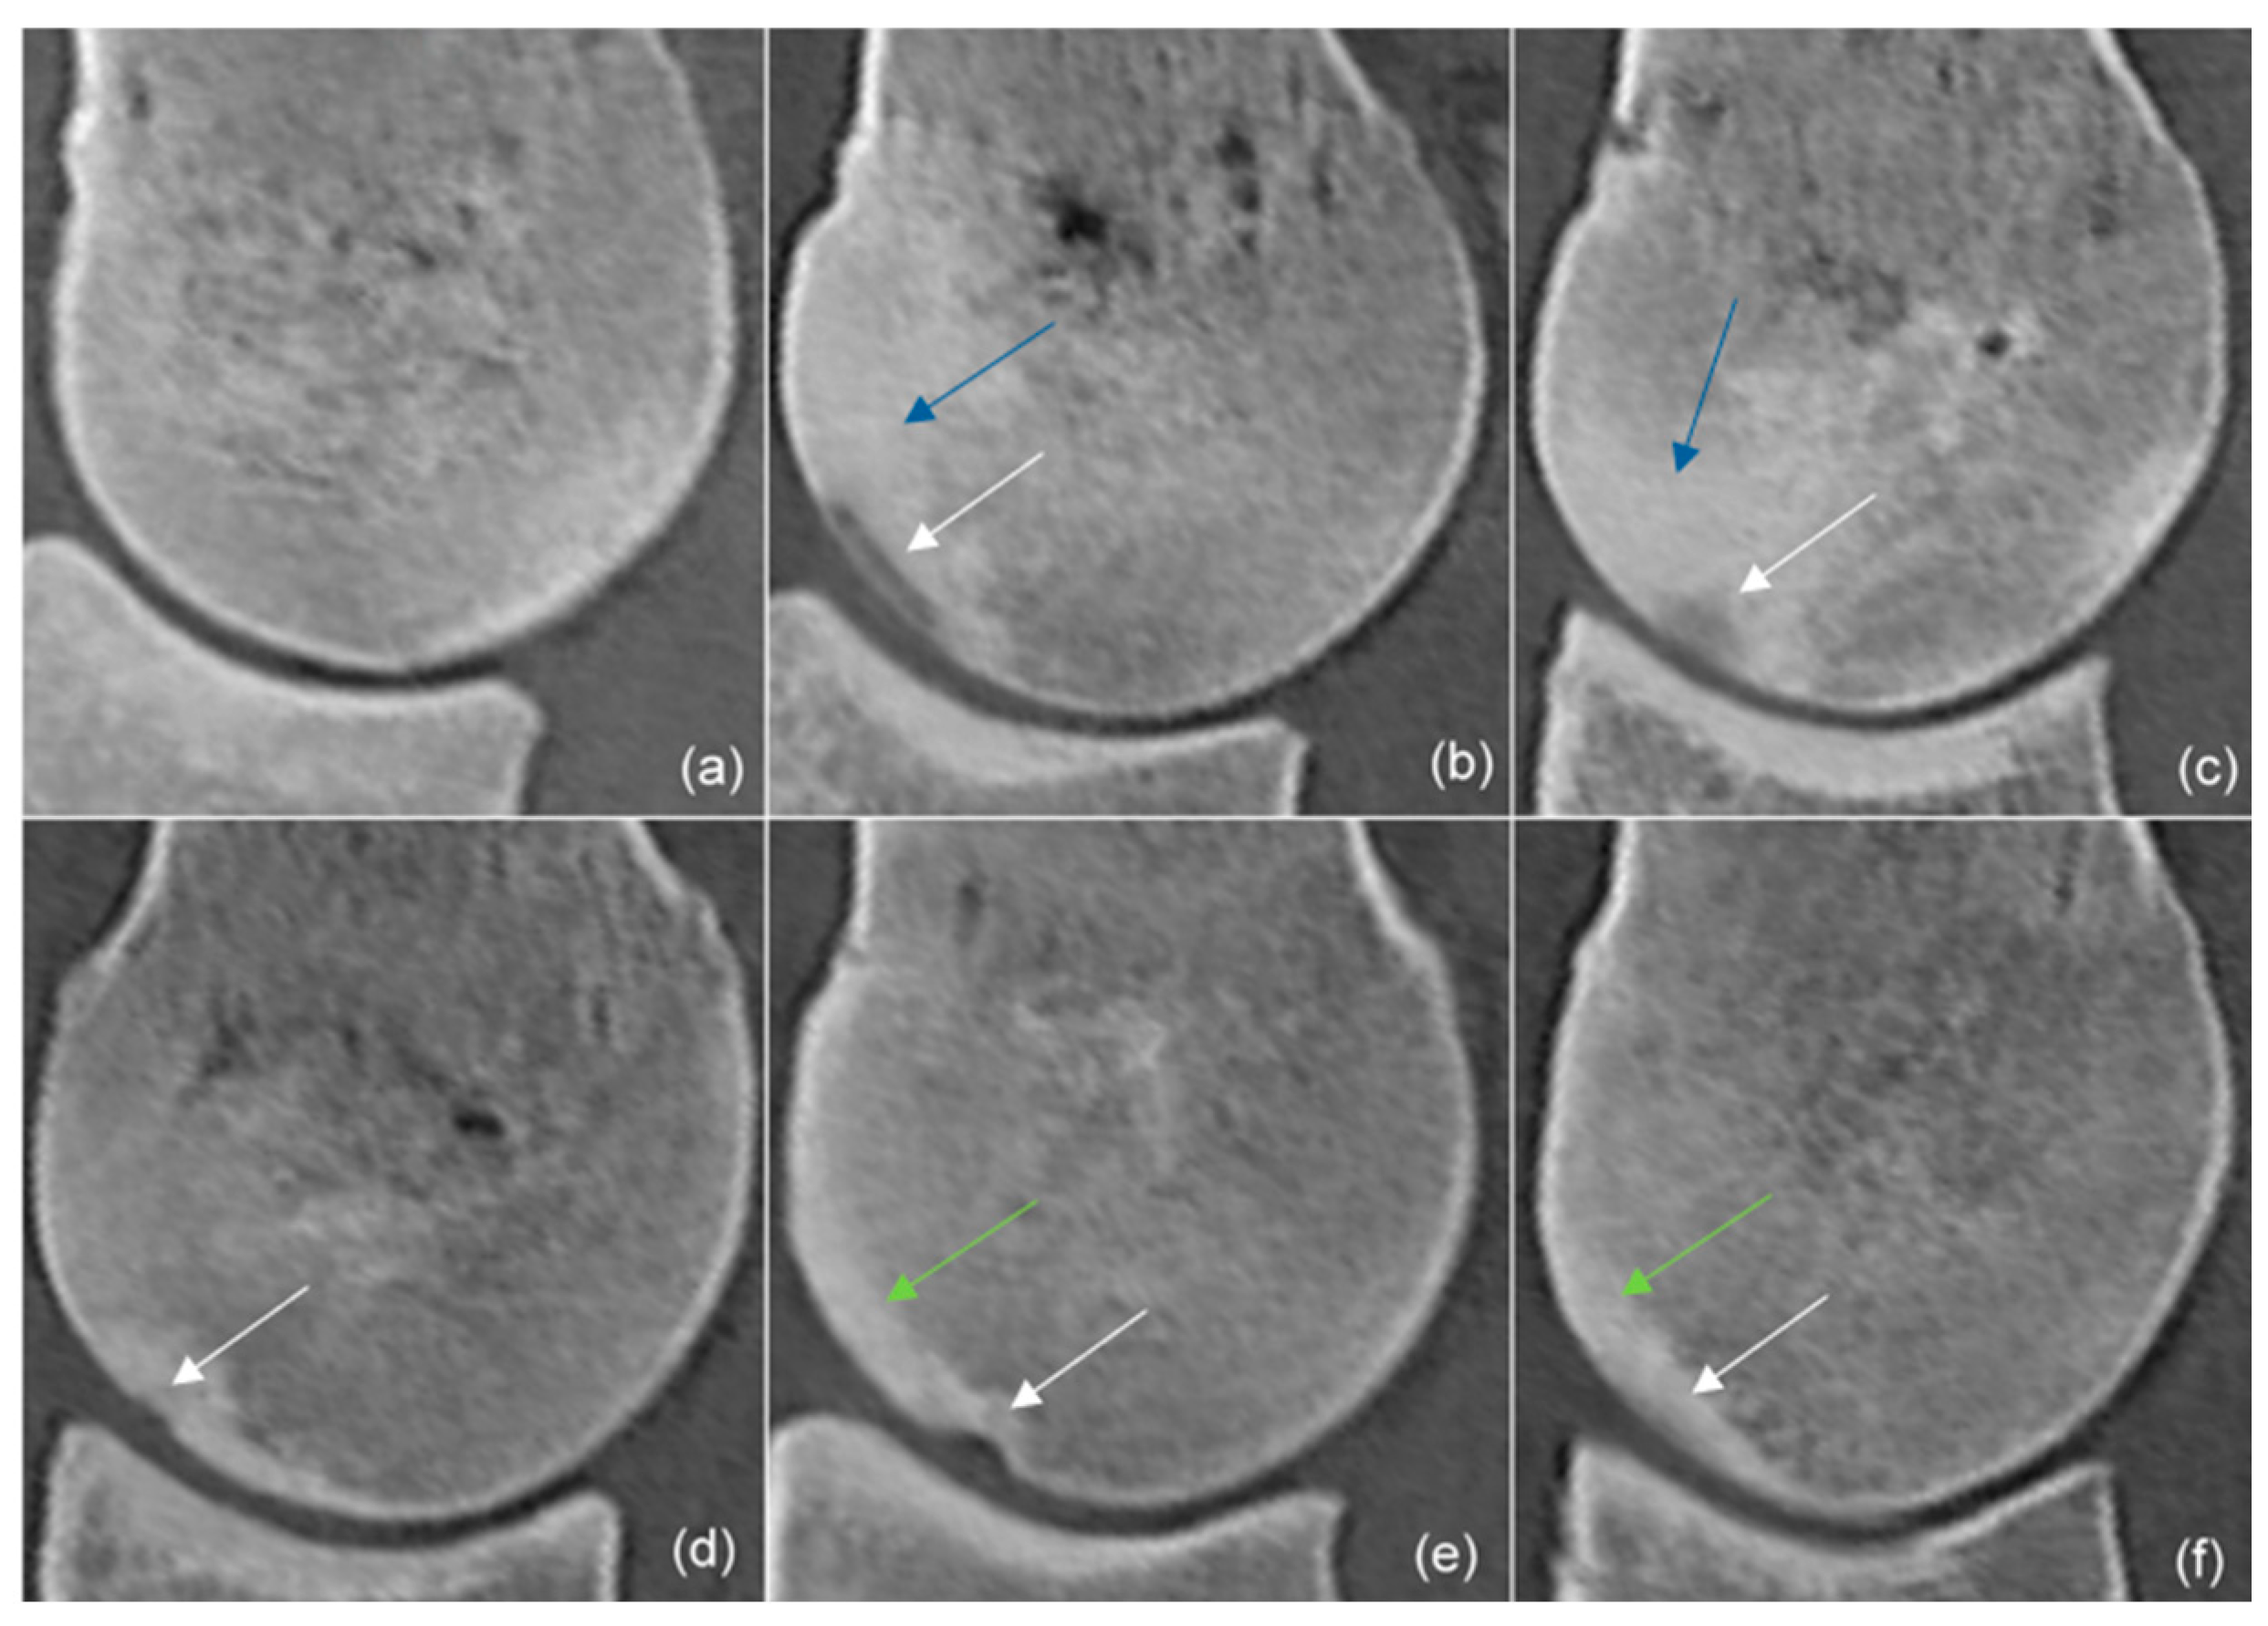

3.4. Subchondral Bone Thickening, Trabecular Bone Hyperattenuation

| Shape | ||||

| Proximodistally elongated | 12 | 6 | 5 | |

| Extending towards trabecular bone | 16 | 10 | 5 | |

| Depression | 1 | 1 | 1 | |

| Indentation | 2 | 1 | 1 | |

| Subtle | 2 | 4 | 2 | |